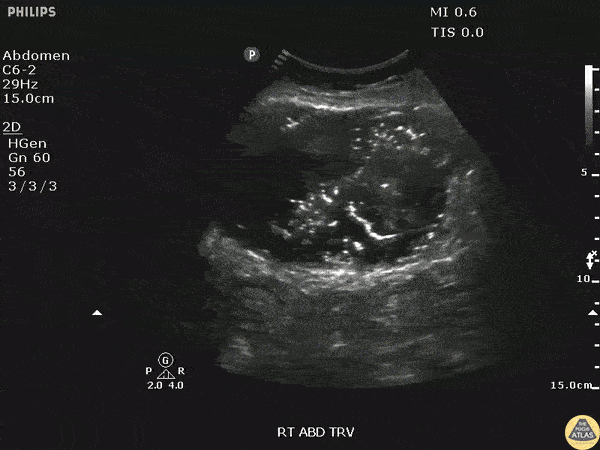

A middle aged female with a history of Crohns disease presented to the ED with fever, hypotension, and abdominal pain. Bedside ultrasound revealed an intra-abdominal abscess in the RUQ. Image courtesy of Robert Jones DO, FACEP @RJonesSonoEM Director, Emergency Ultrasound; MetroHealth Medical Center; Professor, Case Western Reserve Medical School, Cleveland, OH View his original post here